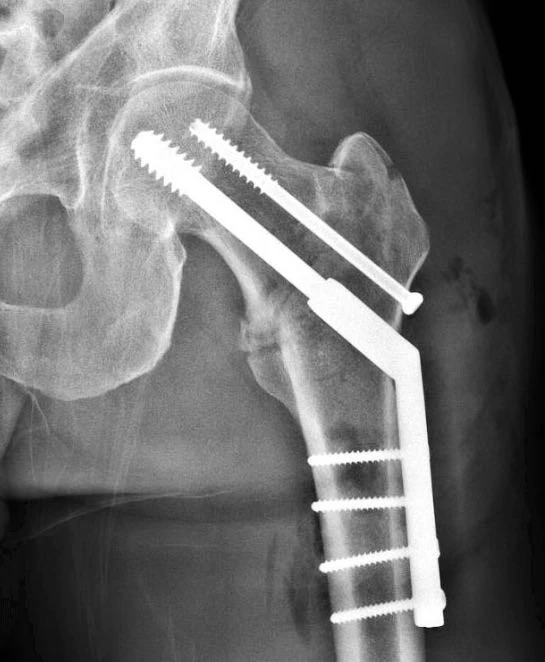

I had my hardware removed 18 months after surgery. The only difference between your x-ray and mine is you have the additional compression screw on top of the huge “main” screw. Don’t get me wrong. I’m VERY glad to have had the hardware taken out, but what I did not expect was the “doctor’s orders” following the removal surgery. No bike racing for more than a year afterward. Crashing would be “bad” Why? Because the significant holes left in the bone (post-surgery). They have to not only fill in, but they must also solidify… and that takes time. The bone, post-removal is very vulnerable to breaking, at least for a whle. I kept my hardware after the surgery. Very cool. Like a fine Campagnolo component. The screws are not at all unlike drywall screws.